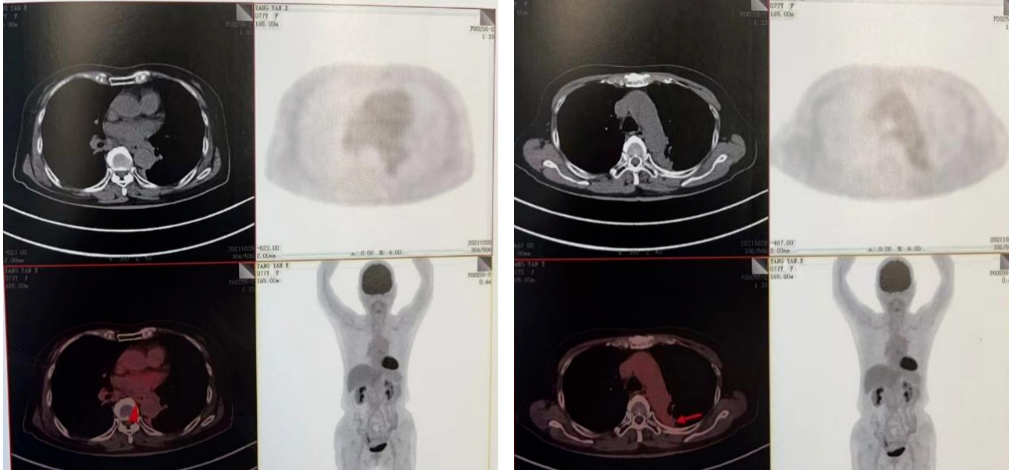

PET-CT(2020-08-13):食管胸下段管壁不均匀增厚,见放射性摄取增高,大小约18×14×27mm,SUVmax 14.6,符合食道癌表现。右侧肺门及纵隔(4R、5、7区)可见多个稍肿大淋巴结,最大约8×5mm,考虑炎性淋巴结可能性大。

左肺上叶尖后段团块状密度增高影,PET见放射性摄取增高,大小约40×29×31mm,SUVmax 28.0。病灶跨越左侧斜裂胸膜生长,密度均匀。左肺上叶胸膜下可见多发微小结节状密度增高影。建议治疗后复查,必要时活检排外恶性肿瘤的可能。

2021-10-28外院PET-CT:原食管胸下段管壁高代谢灶较前缩小,放射性较前减低,现大小约15×17×17mm,SUVmax 3.1,考虑为治疗后改变。左肺上叶团块状高代谢灶较前缩小,放射性摄取较前减低,现大小约25×18mm,SUVmax 2.1,考虑为治疗后改变。

2022-03-28 PET-CT:1、食管癌放化疗后,食管胸中段管壁不规则增厚伴结节状代谢增高,与上次(2021-10-28)PET/CT检查对比,病灶代谢较前明显增高,考虑为肿瘤复发病灶。2、左肺癌放疗后及靶向药治疗后,原左肺上叶团块状高代谢“肿瘤灶”,现范围较前稍缩小,代谢较前稍减低,考虑为治疗后改变(肿瘤完全活性受抑,伴少许炎性反应可能)。